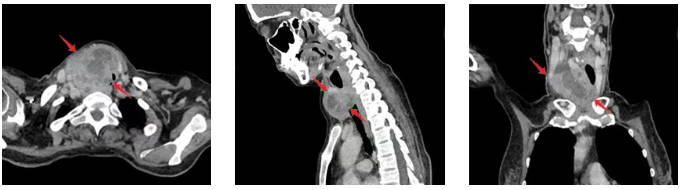

术前CT影像(红箭头示肿物)

耳鼻咽喉科殷玉林教授在门诊接诊后,详细询问病史并认真分析病情,结合初步检查结果,判断情况复杂严重,立即联系科主任王琰教授进行会诊。王琰教授团队考虑到该肿物恶性程度高、进展迅速、可能伴有毗邻器官受累,进一步进行增强CT、喉镜等检查,结果显示该肿物不仅体积巨大,而且侵及了气管及周边组织,同前片比较发现进展极快,必须立刻收治。

对于此类疾病,常规手术方案往往需要切除部分甚至全部喉组织——这会导致患者术后丧失喉功能,造成语言交流能力丧失、吞咽及呼吸功能受损等诸多问题,生活质量将大打折扣。为了寻求最佳方案,耳鼻咽喉科王琰教授迅速牵头组织全院多学科会诊(MDT)。来自耳鼻咽喉科、甲状腺外科、肿瘤内科、放射治疗科、病理科等多个科室的专家齐聚一堂,反复研究影像资料,详细分析患者病情、肿瘤位置、大小及侵袭范围等。经严谨评估,MDT专家团队认为,患者虽病情复杂,但仍有保留喉功能的可能,并根据患者病情制定了详细的手术方案,力求在彻底切除肿瘤的同时最大程度保留喉功能。